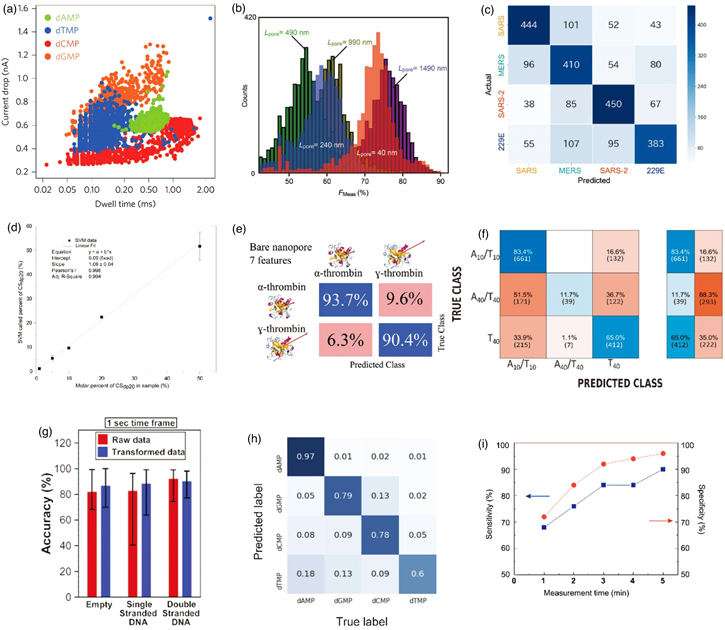

Typical features, such as the peak current (Ip) and current duration (td), have been employed to identify analyte molecules. Before the introduction of the machine and deep learning, the identification of biomolecules was almost exclusively discussed using the histograms of both features. In a recent representative example, four nucleotides were identified using the nanopore of MoS2 (diameter = 2.8 nm, Fig. 7(a). 28) Four oligonucleotides consisting of 30 base molecules were also identified using a nanopore with a diameter of 1.5 nm. During this single-molecule identification, a technique was employed to reduce the translocation speed of the analyte molecule by introducing IL to the cis chamber. In the measurements employing nanopores without controlling the translocation speed of the analyte molecules, analyte molecules of similar sizes yielded largely overlapping Ip and td histograms. Large overlapping histograms complicate the identification of single molecules. It is also challenging to quantitatively assess the accuracy of identifying analyte molecules based on the histograms of Ip and td. To practicalize the methods for testing proteins, viruses, and bacteria, the analyte molecules in a single microtube must be identified with a high degree of accuracy. Particularly, the high-precision discrimination of the analytes that are only present in trace quantities in a single microtube is strongly required for practical application. A high degree of accuracy must be achieved in the identification of a single analyte molecule, following the ionic current–time waveforms of several analyte molecules. Put differently, the accuracy of identifying one analyte molecule using one ionic current–time waveform is essential.

Fig. 7. (Color online) Identification of the analyte molecules. (a) Analysis using typical nonmachine learning. Single-molecule identification employing changes in the current and current duration (four nucleotides were identified). Reprinted with permission from Ref. 28. Copyright 2015 Springer Nature. (b) Identification of E. coli and B. subtilis using Rotation Forest. Histogram of the discrimination accuracy in nanopores exhibiting different thicknesses. Reprinted with permission from Ref. 41. Copyright 2017 Springer Nature. (c) Identifications of four cultured coronaviruses by Random Forest. Confusion matrix resulting from machine learning. Reprinted with permission from Ref. 44. Copyright 2021 Springer Nature. (d) Identifications of two glycosaminoglycan species via SVM. Relationship between the amount of the two glycosaminoglycan species in the mixed solution and the amount estimated by machine learning. Reprinted with permission from Ref. 140. Copyright 2019 American Chemical Society. (e) Identification of proteins via SVM. Confusion matrix obtained by the machine learning of the ionic current–time waveforms of α-thrombin and γ-thrombin. Reprinted with permission from Ref. 141. Copyright 2021 American Chemical Society. (f) Identification of three DNA species employing SVM. Reprinted with permission from Ref. 142. Copyright 2020 MDPI. (g) Identification of three viruses by DNNs. The accuracy of identifying the three viruses: empty indicates adenoviruses that do not encapsulate DNA, and the other two indicate adenoviruses encapsulating single-stranded DNA (ssDNA) and dsDNA. Reprinted with permission from Ref. 143. Copyright 2020. The Royal Society of Chemistry. (h) Identifications of four nucleotide species by DNNs. Confusion matrix obtained via deep learning. Reprinted with permission from Ref. 144. Copyright 2021 American Institute of Physics. (i) Discrimination of the PCR-positive and PCR-negative saliva specimens for SARS-CoV-2 by machine learning. Time dependence of the sensitivity and specificity. Reprinted with permission from Ref. 44. Copyright 2021 Springer Nature.

Standard image High-resolution imageIn the machine and deep learning of ionic current–time waveforms, an F-measure is defined as the accuracy with which n analyte molecules can be identified in a single waveform. The F-measure is calculated from the confusion matrix. When the F-measure is 1, the discrimination accuracy is 100%. Thus, n analyte molecules are identified when the F-measure is greater than 1/n. The open library, scikit-learn, 139) is widely employed for machine and deep learning programs. E. coli and Bacillus subtilis were identified with an F-measure = 0.90 via machine learning using Rotation Forest on the ionic current–time waveforms obtained from nanopores exhibiting a diameter of 3 m [Fig. 7(b)]. 41) Cultured SARS-CoV, MERS-CoV, SARS-CoV-2, and HEP-229E have been identified with an F-measure = 0.66 employing Random Forest with nanopores having a diameter of 300 nm [Fig. 7(c)]. 44) Two glycosaminoglycans have been identified using nanopores (diameter = 2.7 nm) and a support vector machine (SVM) with an F-measure of >0.94. 140) In mixed solutions containing both glycosaminoglycan types, machine learning estimated the mixing ratio [Fig. 7(d)]. Using nanopores (diameter = 12 nm) and SVM, α-thrombin and γ-thrombin were identified with an F-measure of 0.93 [Fig. 7(e)]. 141) Three dsDNA consisting of 10 and 40 bases were also identified with an F-measure of 0.82 by SVM with nanopores exhibiting diameters of 2 and 4 nm, respectively [Fig. 7(f)]. 142) Adenoviruses with and without DNA were identified by nanopores (diameter = 100 nm) and deep neural network (DNN) with an F-measure of ≥0.95 [Fig. 7(g)]. 143) Four nucleotides were identified with F-measures of ≥0.94 by MoS2 nanopores with diameters of 2.8 and 3.3 nm, as well as DNN and convolutional NNs (CNN) [Fig. 7(h)]. 144) The measurements also demonstrated the control of the translocation speed of the analyte molecules by IL. These machine learning techniques ensure the accuracy of identifying the analyte molecules obtained using a single ionic current–time waveform.

Clinical saliva specimens that were PCR-positive and PCR-negative for SARS-CoV-2 were measured in nanopores with a diameter of 300 nm at 5 min/specimen. 44) For the training process, 40 PCR-positive and 40 PCR-negative specimens were used, and for the diagnostic process, 50 PCR-positive and 50 PCR-negative specimens were employed. The discrimination accuracy employing Random Forest and positive unlabeled classification (PUC) 145,146) of positive and negative by one ionic current–time waveform was F-measure = 1.00 in the training process. The PUC method learns the ionic current–time waveforms of the impurities in the negative specimens and extracts them from the waveforms obtained from the positive specimens. The ensemble learning of all the ionic current–time waveforms obtained for each specimen exhibited a sensitivity and specificity of 90% and 96%, respectively, for determining the positive and negative results [Fig. 7(i)]. 44)